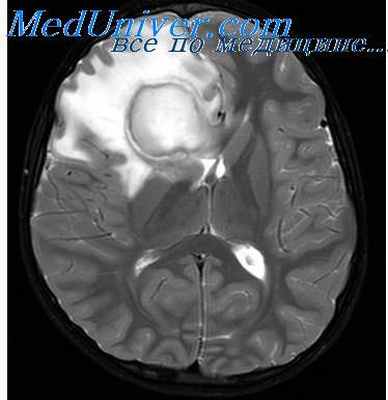

Начальная стадия соответствует ограниченному энцефалиту (церебриту) и обычно характеризуется не резко выраженными изменениями неспецифического характера на фоне обострения хронического гнойного среднего отита – нелокализованной головной болью, недомоганием. Впоследствии происходит ограничение (барьеризация) воспалительного процесса, сопровождаемое минимизацией клинических проявлений заболевания (латентная стадия). Для этого периода характерно отсутствие какой-либо отчетливой симптоматики. Важными клиническими признаками сформированного абсцесса мозга (явная стадия) являются общеинфекционые (слабость, повышение температуры тела, изменения в периферической крови), общемозговые (головная боль, тошнота, рвота, брадикардия, застойные изменения на глазном дне) и очаговые симптомы. Последние зависят от локализации абсцесса. К признакам абсцесса височной доли относят контрлатеральный гемипарез, центральный паралич лицевого нерва, судороги, атаксию, нарушения вкуса и обоняния, гомонимную гемианопсию, алексию, аграфию, а при поражении доминантной доли – сенсорную и амнестическую афазию. К очаговым симптомам абсцесса мозжечка относят координационные расстройства, понижение сухожильных рефлексов на стороне поражения, появление патологических рефлексов и др. При вторичном гнойном менингите у больных с абсцессом мозга наблюдается менингеальный синдром с характерными изменениями спинномозговой жидкости. Вместе с тем многообразие клинических проявлений отогенного абсцесса мозга, его частое сочетание с другими внутричерепными осложнениями затрудняют своевременную диагностику. Именно поэтому одним из наиболее эффективных методов диагностики отогенных абсцессов мозга является КТ [24–26]. При проведении КТ визуализируется участок мозга пониженной плотности с ровными краями и выраженной зоной перифокального отека, усилением визуализации капсулы при введении контрастного вещества [27].

По оценкам экспертов, высокой, сопоставимой с КТ чувствительностью при абсцессах мозга обладает МРТ. При абсцессах мозга на стадии церебрита чувствительность МРТ превышает чувствительность КТ [29].

Для того чтобы провести точную диагностику места расположения абсцесса мозга и мозжечка, проводят компьютерную и магнитно-резонансную томографию головного мозга. При проведении компьютерной томографии выявляется тонкая, гладкая стенка абсцесса, которая имеет правильные контуры. Магнитно-резонансная томография позволяет также определить капсулу абсцесса. Если нет возможности провести вышеперечисленные виды исследования, можно провести пневмоэнцефалографию или радиоизотопную сцинтиграфию головного мозга.